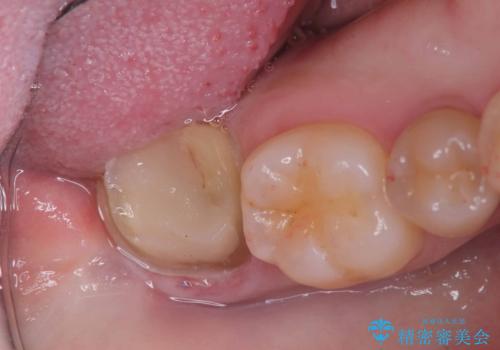

- 頬側に大きな虫歯があり、神経に達している可能性が高かったため、虫歯除去時に神経が出た場合はVPTを提案しました。

虫歯が神経まで達していましたが、術前の検査でVPTの適応と診断をしていたので、ラバーダムシートを装着しVPTを行いました。

経過も良好で、痛みも無く神経を残すことが出来ました。